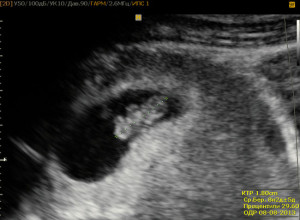

Знімки УЗД на 8 тижні вагітності